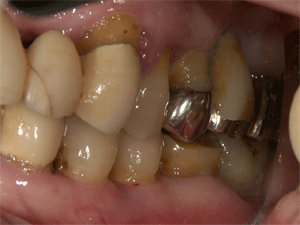

最新の写真です

上顎のブリッジを治しました   比較的よく歯ブラシできるようのなりました   残念なことに左下の7番(1番奥の歯)が抜歯になってしまいました。下顎は義歯を使用されています。